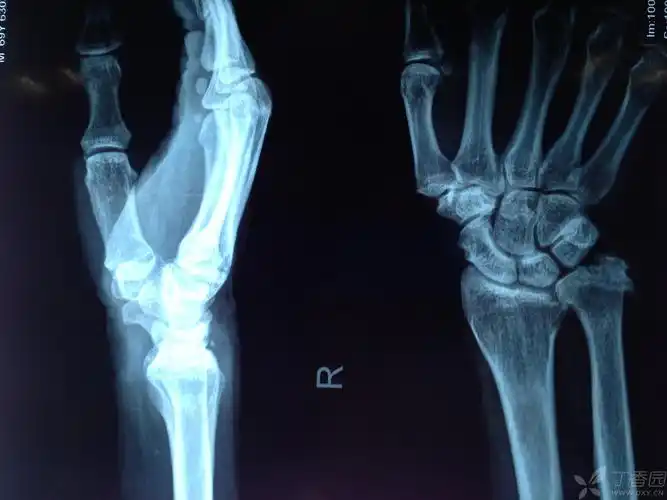

右尺骨茎突撕脱骨折?

右尺桡骨茎突骨折月骨周围脱位

男,27岁 下楼梯摔倒,手掌撑地.诊断:右挠骨远端骨折,尺骨茎突骨折.